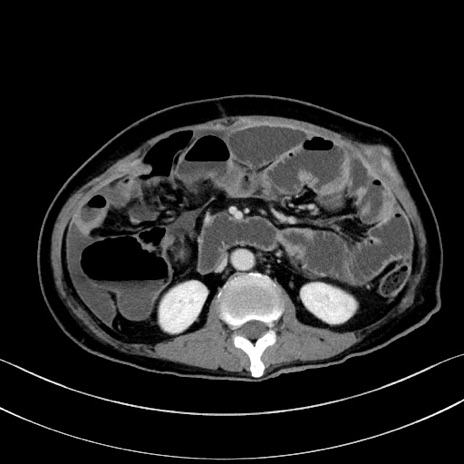

症例28(横断像)

【症例】60歳代男性

【主訴】嘔吐

【現病歴】胃癌にて胃全摘後。食思不振が悪化し、夜中に嘔吐することがある。

【既往歴】胃癌、胃全摘、脾摘、胆摘後

【データ】WBC 5900、CRP 10.56